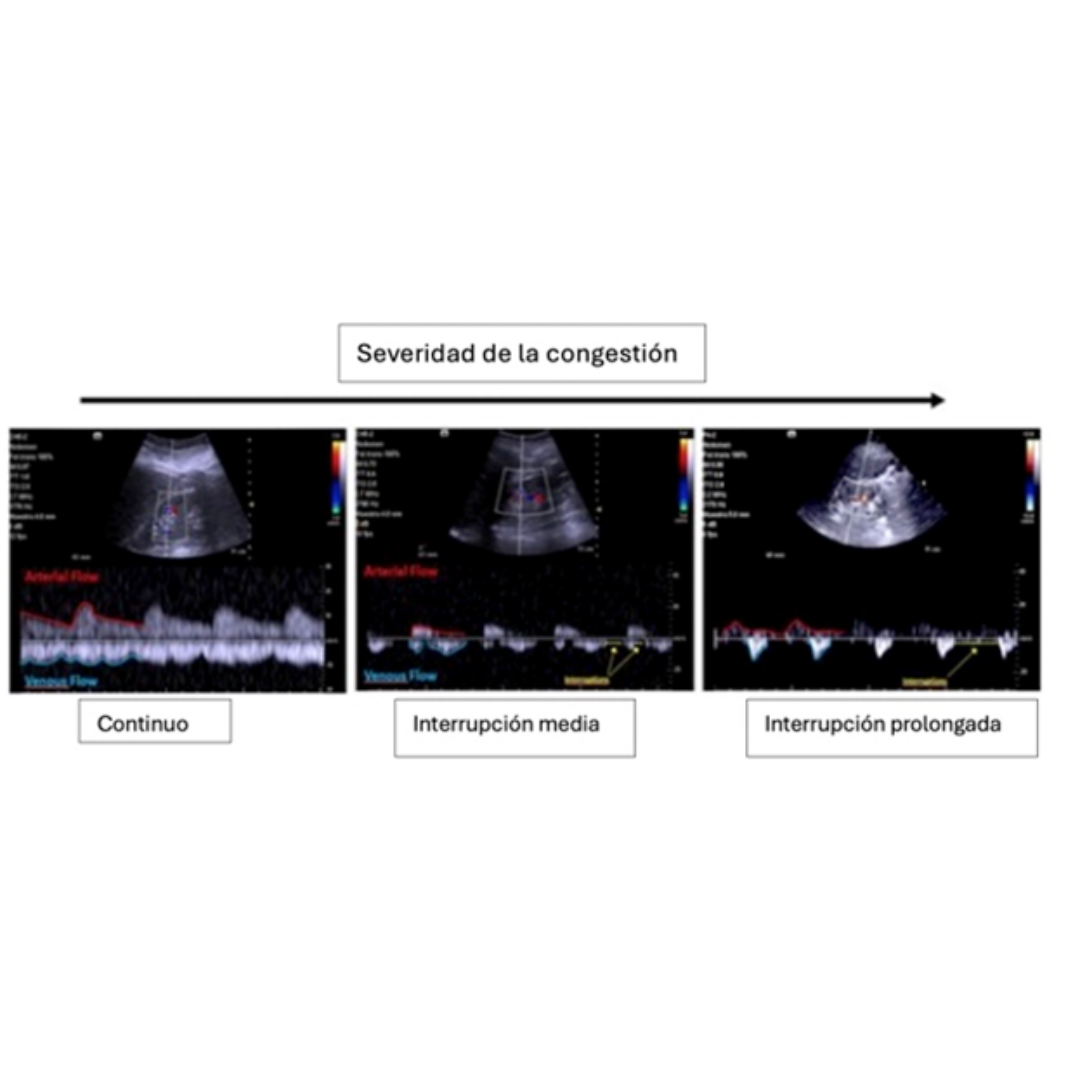

Figura 16: Evaluación del flujo venoso renal en presencia de congestión. En condiciones normales el flujo es continuo y puede observarse por debajo, con una línea azul, A medida que hay mayor congestión sistémica se vuelve bifásico o monofásico. (4)